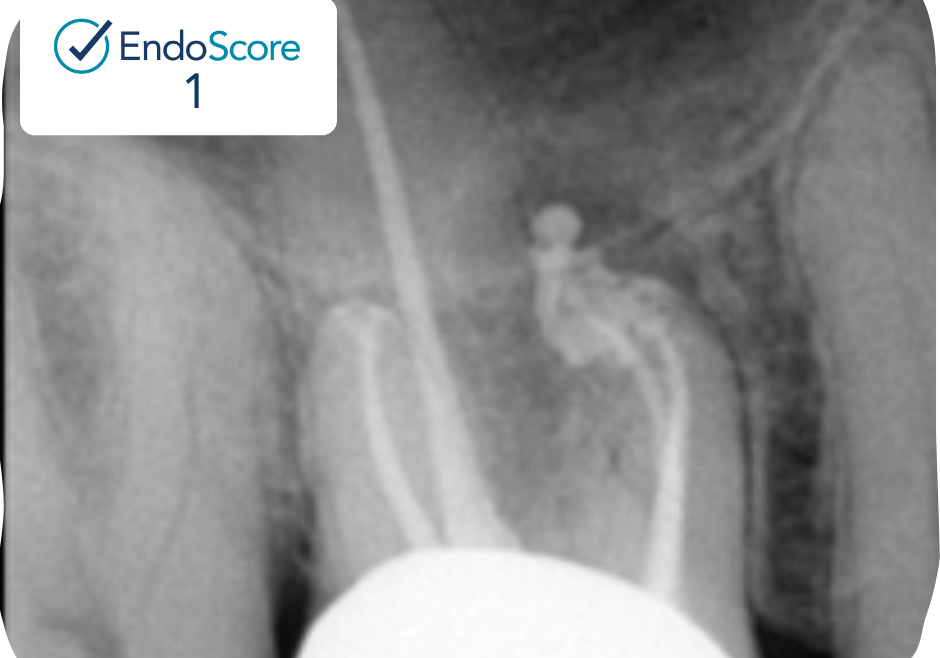

Case Study by Dr. Justin Kolnick

Endoscore of 69 was reduced to a final score of Endoscore 1 after MB2 canal was located and treated.

Obturated with EndoCeramicâ„¢ Sealer (Endo Direct) and single cone gutta percha.

EndoScore: 69 to 1